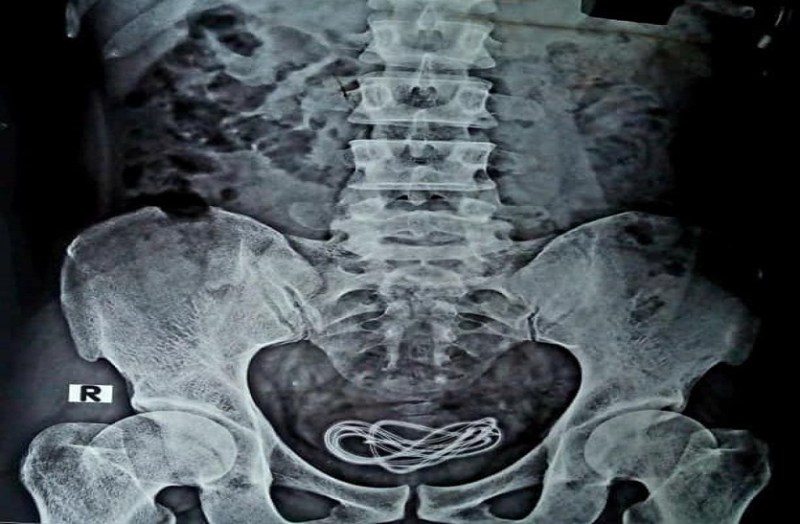

इसके बाद डॉक्टरों ने व्यक्ति की सर्जरी करने का फैसला किया, लेकिन जब डॉक्टर उसकी सर्जरी करने लगे तो उन्होंने देखा कि युवक ने उनसे झूठ बोला था। सर्जरी करने वाले गुवाहाटी के एक प्रसिद्ध सर्जन डॉक्टर वालियुल इस्लाम ने कहा कि 'जब हमने उस व्यक्ति का ऑपरेशन किया, तो पाया कि युवक के गैस्ट्रोइंटेस्टाइनल ट्रैक्ट में कुछ भी नहीं था। सर्जरी के दौरान उन्हें पता चला कि युवक उनसे कुछ छुपा रहा है। दरअसल सर्जरी के दौरान युवक के गैस्ट्रोइंटेस्टाइन ट्रैक्ट में कुछ भी नहीं था। इसके बाद डॉक्टरों ने ऑपरेशन टेबल पर ही युवक का एक्स रे करवाया। इस एक्सरे में मालूम चला कि मोबाइल की केबल उसके पेट में नहीं मूत्राशय के अंदर पड़ी है।

मूत्राशय में मिली केबल

डॉक्टर वालियुल इस्लाम ने कहा, 'मैं करीब 25 साल से सर्जरी कर रहा हूं लेकिन उनके सामने ऑपरेशन टेबल पर इस तरह का यह पहला मामला है। डॉक्टरों ने सर्जरी कर मोबाइल केबल को निकाल लिया है, लेकिन इस घटना ने सभी डॉक्टरों को हैरान कर दिया है। इस युवक ने मुंह के माध्यम से नहीं बल्कि अपने गुप्तांग के जरिए मोबाइल चार्जर केबल शरीर के भीतर डाली थी। डॉक्टरों का कहना है कि शख्स ने यौन आनंद के लिए अपने गुप्तांग के माध्यम से केबल अंदर डाल ली थी लेकिन उसकी यही उसकी सबसे बड़ी भूल हो गई।